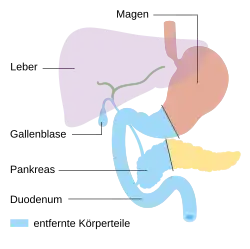

Es ist sinnvoll, möglichst einen Teil des Organs zu erhalten und wieder mit dem Darm zu verbinden. Je nach Ort des Tumors wird deshalb die rechtsseitige Teilresektion (Duodenopankreatektomie, mehrere Varianten), eine mittlere Teilresektion, eine linksseitige Teilresektion (Pankreasschwanzresektion, meist mit Entfernung der Milz) oder eine Totalresektion (vollständige Entfernung) der Bauchspeicheldrüse durchgeführt, meist einschließlich aller regionären Lymphknoten. Der Magen und der Gallengang müssen wieder mit dem Darm verbunden werden. Man verwendet dafür entweder eine oder mehrere hochgezogene Dünndarmschlingen, die spannungsfrei angeschlossen werden. Bei der Verwendung mehrerer Dünndarmschlingen werden diese rekonstruiert nach der klassischen von César Roux erdachten Methode. Nach Teilresektion kann der Ausführungsgang des belassenen Rests der Bauchspeicheldrüse sowohl mit dem Dünndarm als auch mit dem Magen verbunden werden.

Totale Pankreasresektion

Totale Pankreasresektion -

Endzustand nach Totalresektion

Endzustand nach Totalresektion

Die subtotale oder totale Pankreasentfernung bringt als Maximaleingriff die höchste Letalität mit sich. In etwa 6 % der Operationen kommt sie zum Einsatz. Gefürchtete Komplikation ist der schwer einstellbare Brittle-Diabetes.